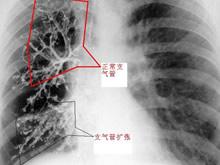

۞ 急性气管支气管炎的辅助检查